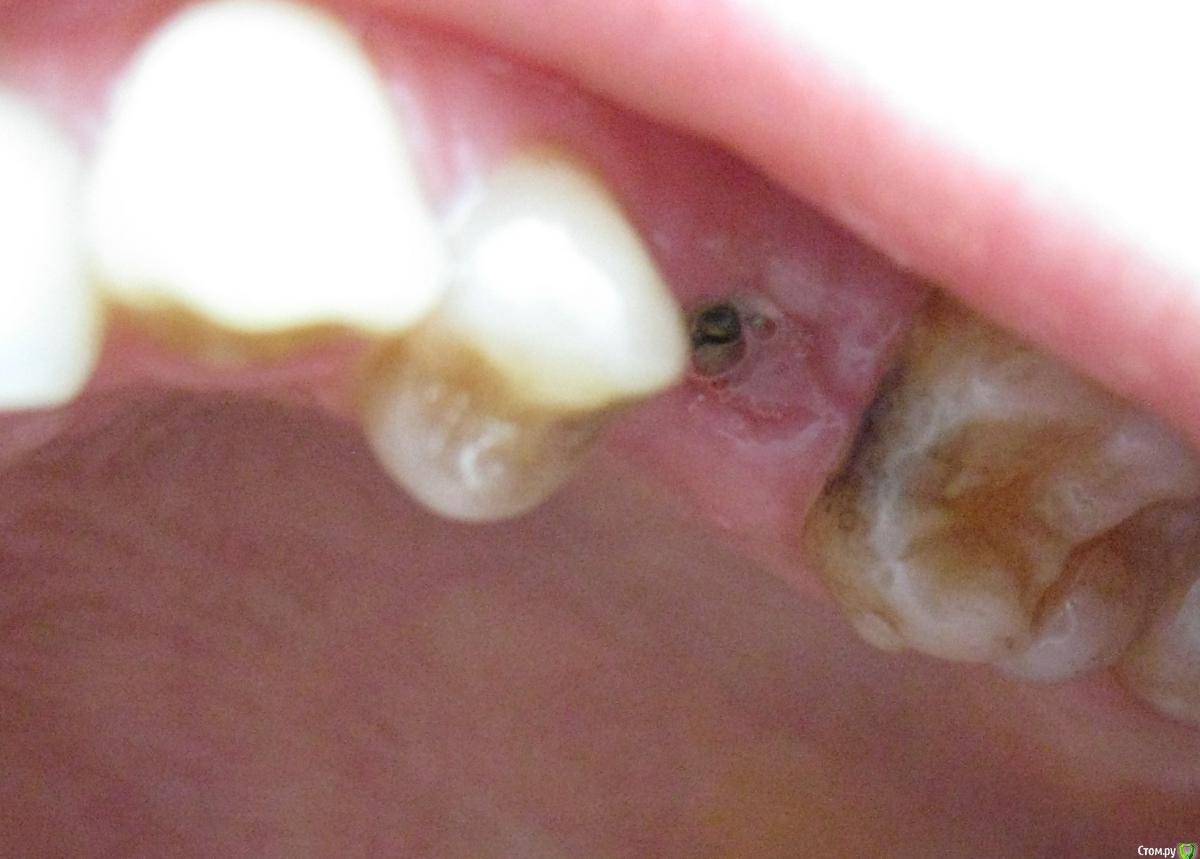

Natalia_ Опубликовано 4 апреля, 2015 Поделиться Опубликовано 4 апреля, 2015 Уважаемые специалисты,посмотрите, пожалуйста, стоит мне из-за этого беспокоиться или не все так страшно. 2 недели назад имплантация, 5-ка, вчера сняли швы - и я вижу имплант над десной..(Под швами не знаю что было, не приглядывалась) Вроде так не должно быть? Будет заметен абатмент потом над коронкой (и портить мне настроение), если так оставить? Чего с ним делать - удалять и переделывать или не все потеряно. Что посоветуете? Переделывать страшно, но чтобы видно было - не хочу... Ссылка на комментарий

Natalia_ Опубликовано 6 апреля, 2015 Автор Поделиться Опубликовано 6 апреля, 2015 Была сегодня у хирурга. Говорит, все у меня хорошо, швы не разошлись, никакой имплант наружу не торчит, десна еще будет зарастать, и поменьше надо в рот смотреть. Озадачена. Видно же имплант? Резьбу блестящую вчера видела. (Сейчас синей мазью замазано после осмотра). Ну, я конечно, рада, если у меня все хорошо ... Подскажите, пожалуйста, уважаемые специалисты-имплантологи, вы кто-нибудь вот так импланты оставляете? Зарастет он у меня или так останется? (или десна наоборот просядет?) Ссылка на комментарий

Aquarius Опубликовано 6 апреля, 2015 Поделиться Опубликовано 6 апреля, 2015 Так мне говорят, что не разошлись швы-то...( И формирователь ставить не собираются. Говорят - так ходить...Я ж сама себе не зашью и не поставлю. И другой хирург вряд ли возьмется. Может там действительно торк этот маленький и вылетит все к .Конечно Ваши фото не показательны. Но мажьте на всякий случай метрогилом плюс солкосерил дентальный. Похоже,что и само закроется. Ссылка на комментарий